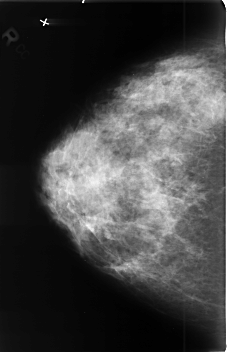

B_3409_1.RIGHT_MLO

RIGHT_CC LINES 4576 PIXELS_PER_LINE 2944 BITS_PER_PIXEL 12 RESOLUTION 50 NON_OVERLAY

RIGHT_MLO LINES 4544 PIXELS_PER_LINE 2800 BITS_PER_PIXEL 12 RESOLUTION 50 NON_OVERLAY